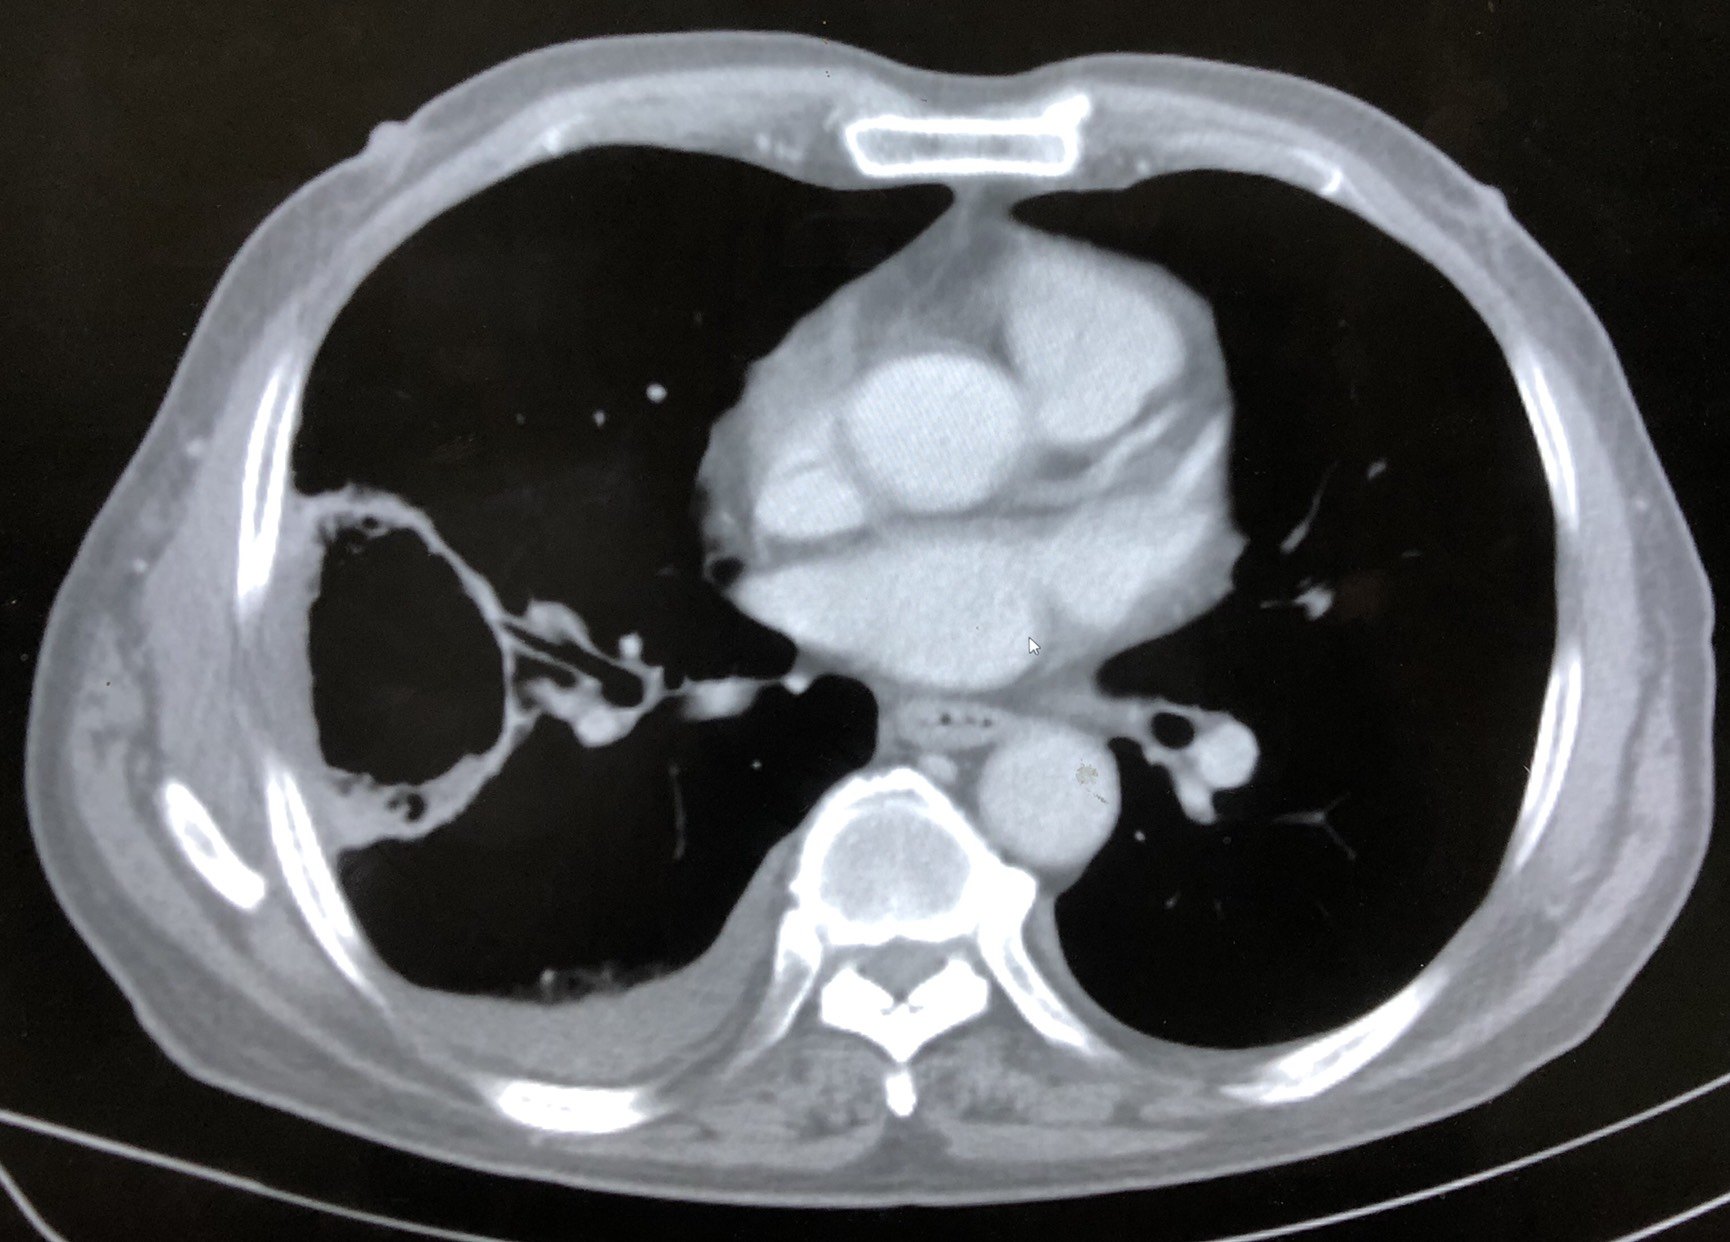

图2 氩氦刀冷冻消融治疗同时肺活检术,见冰球基本覆盖肿瘤。